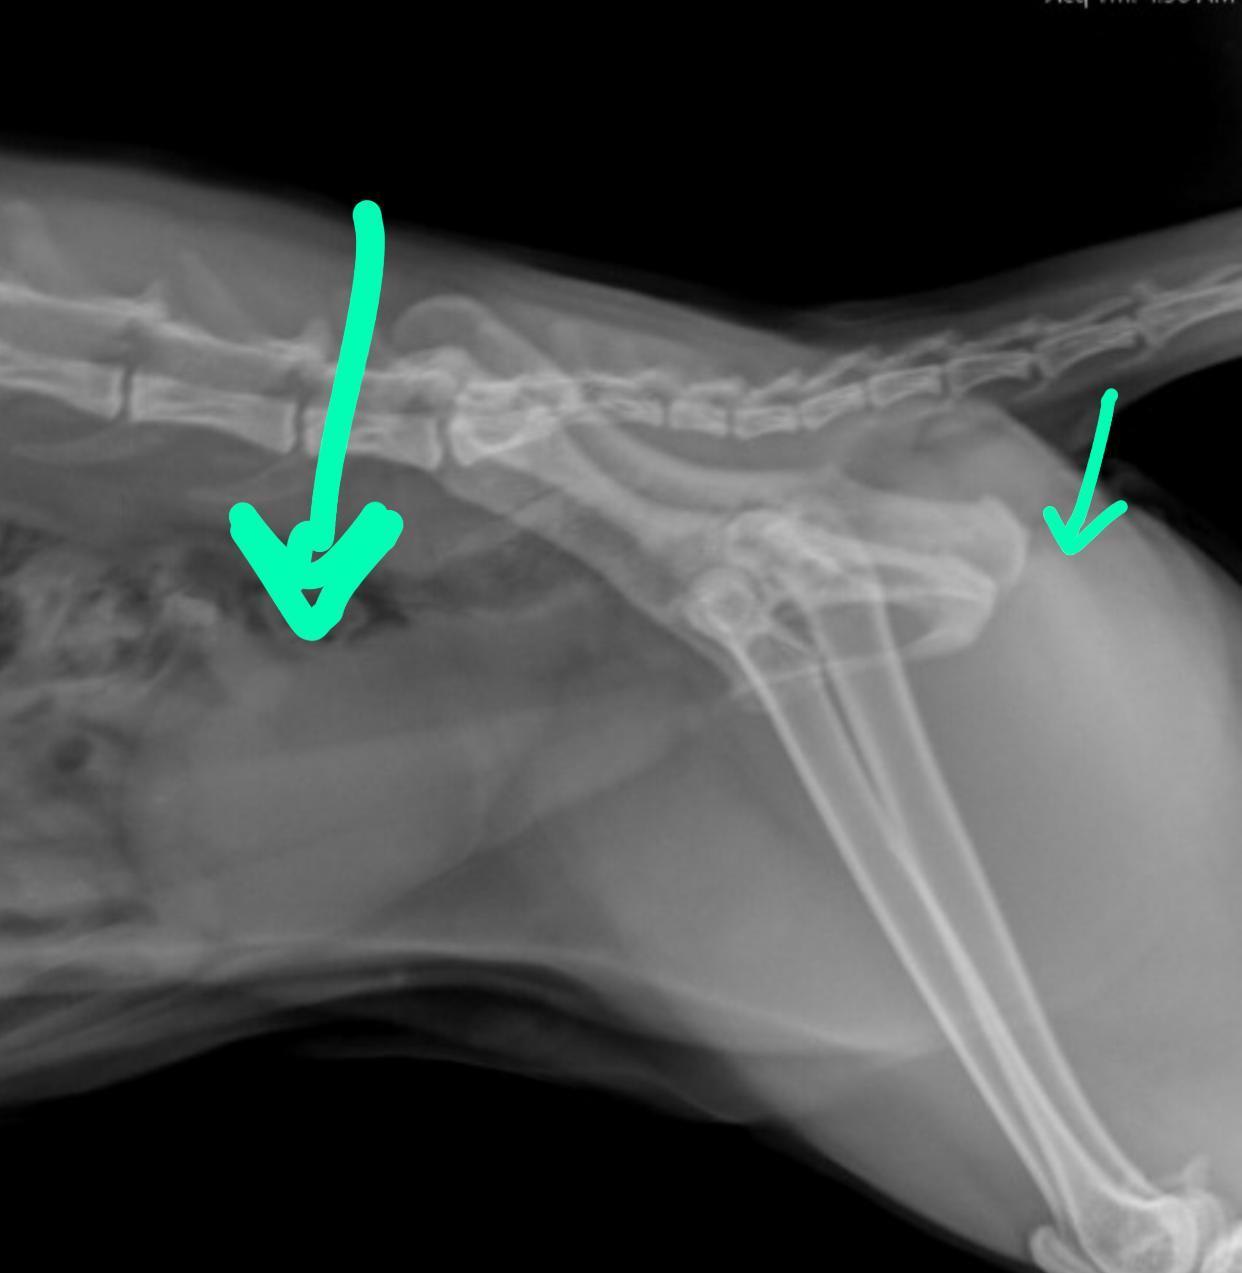

Hello and thank you for contacting Petco Pet Education Center, formerly Petcoach. It is very hard to see on the attached x-ray if there is any problem with the urinary tract or. Some of the bladder stones come up on a plain x-ray and can be easily seen. I cannot see any obvious stone obstructing the bladder / urethra. However, some stones are radiolucent (do not come up on x-rays) and the cat would need a constrast x-ray or ultrsound of the bladder to detect them. In general, urethral blockage in young female cats are very uncommon. If Marshy is able to pass urine, other urinary tract diseases should be investigated. Urine analysis should be the next step of investigation (to rule in/out infection or bladder crystals) followed by an ultrasound of the abdomen and a blood test.